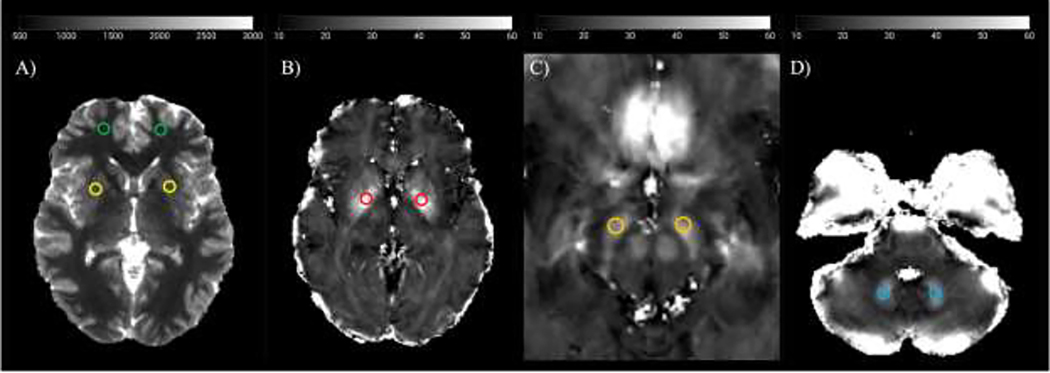

Description:Inhalation of welding fumes can cause metal accumulation in the brain, leading to Parkinsonian-like symptoms. Metal accumulation and altered neurochemical profiles have been observed using magnetic resonance imaging (MRI) in highly exposed welders, being associated with decreased motor function and cognition. While MRI is impractical to use as a health risk assessment tool in occupational settings, toenail metal levels are easier to assess and have been demonstrated to reflect an exposure window of 7-12 months in the past. Yet, it is unclear whether toenail metal levels are associated with brain metal levels or changes in metabolism, which are the root of potential health concerns. This study investigates whether toenail manganese (Mn) and iron (Fe) levels, assessed at several time points, correlate with brain Mn and Fe levels, measured by MRI, as well as brain GABA, glutamate (Glu), and glutathione (GSH) levels, measured by Magnetic Resonance Spectroscopy (MRS), in seventeen Mn-exposed welders. Quantitative T1 and R2* MRI maps of the whole brain, along with GABA, Glu, and GSH MRS measurements from the thalamus and cerebellum were acquired at baseline (T0). Toenail clippings were collected at T0 and every three months after the MRI for a year to account for different exposure periods being reflected by toenail clippings and MRI. Spearman correlations of toenail metal levels were run against brain metal and metabolite levels, but no significant associations were found for Mn at any timepoint. Cerebellar GSH positively correlated with toenail Fe clipped twelve months after the MRI (p = 0.05), suggesting an association with Fe exposure at the time of the MRI. Neither thalamic GABA nor Glu correlated with toenail Fe levels. In conclusion, this study cannot support toenail Mn as a proxy for brain Mn levels or metabolic changes, while toenail Fe appears linked to brain metabolic alterations, underscoring the importance of considering other metals, including Fe, in studying Mn neurotoxicity.